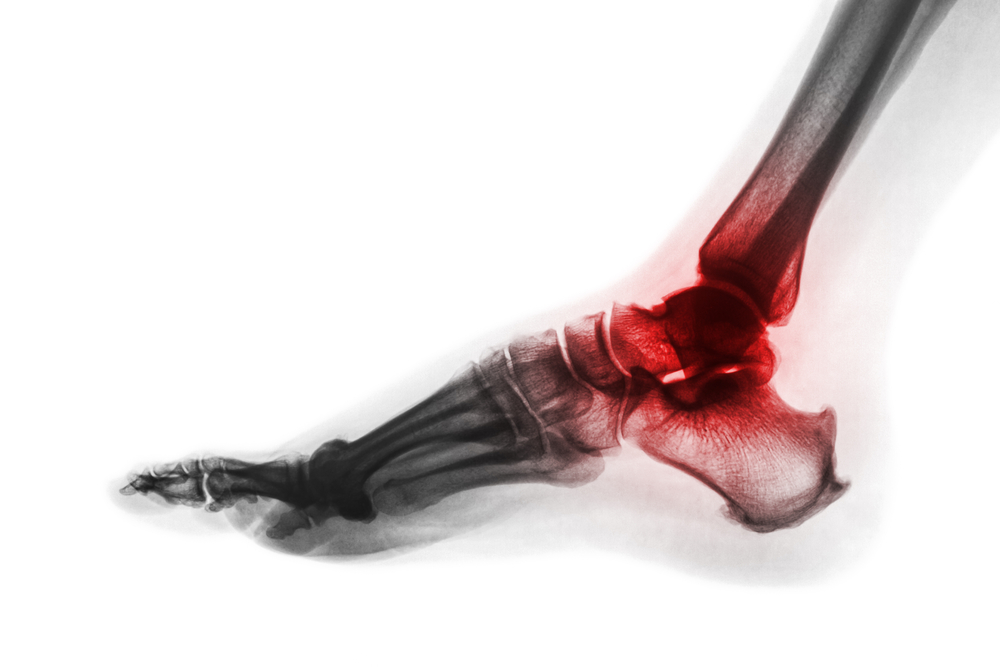

Rheumatoid arthritis can be a debilitating disease where a joint's lining (synovium) is attacked by the body’s immune system. This causes the synovium to become inflamed, which damages the surrounding tissues and ligaments. In time, this may dislocate toe joints and cause deformities such as bunions and hammertoes. Along with toe joints, rheumatoid arthritis can also occur in the ankle joint, the tarsometatarsal joints in the midfoot, and the hindfoot (heel area). While rheumatoid arthritis has no cure, a podiatrist can help treat its symptoms which, if left untreated, may inhibit a person’s ability to lead a normal life. Your podiatrist may prescribe special shoes, braces, and/or create custom orthotics to help restore functionality to the feet and relieve pain. Icing, gentle exercises, and physical therapy may also help relieve symptoms, as can corticosteroid injections. Make an appointment with a podiatrist today to begin treatment for your painful rheumatoid arthritis symptoms.

Rheumatoid Arthritis (RA) is an autoimmune disorder in which the body’s own immune system attacks the membranes surrounding the joints. Inflammation of the lining and eventually the destruction of the joint’s cartilage and bone occur, causing severe pain and immobility.

Although RA usually attacks multiple bones and joints throughout the entire body, almost 90 percent of cases result in pain in the foot or ankle area.

Quick diagnosis of RA in the feet is important so that the podiatrist can treat the area effectively. Your doctor will ask you about your medical history, occupation, and lifestyle to determine the origin of the condition. Rheumatoid Factor tests help to determine if someone is affected by the disease.